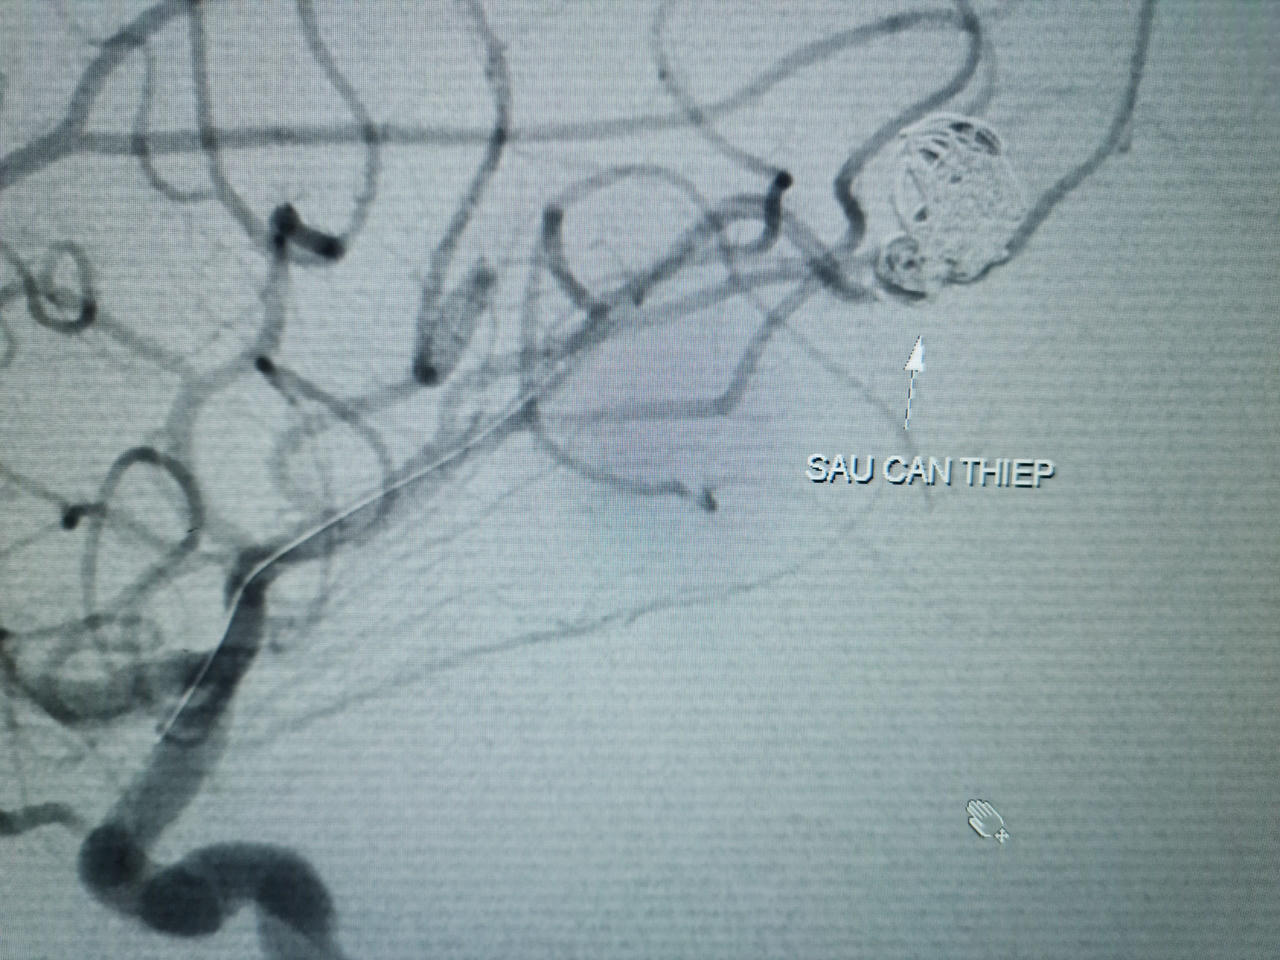

Các bác sĩ đã quyết định chụp mạch máu não bằng kỹ thuật DSA (chụp mạch máu kỹ thuật số xóa nền) để chẩn đoán xác định. Kết quả chụp cho thấy tình trạng xuất huyết não ở bé là do túi phình mạch máu não vỡ. Bệnh nhân được chỉ định nút phình mạch máu não số xóa nền DSA. Quá trình can thiệp đã diễn ra khá thuận lợi và bít được hoàn toàn túi phình. Hiện bé đã ổn định, hết nhức đầu, ăn uống lại tốt.

![]() |

Hình ảnh túi phình mạch máu não sau can thiệp |